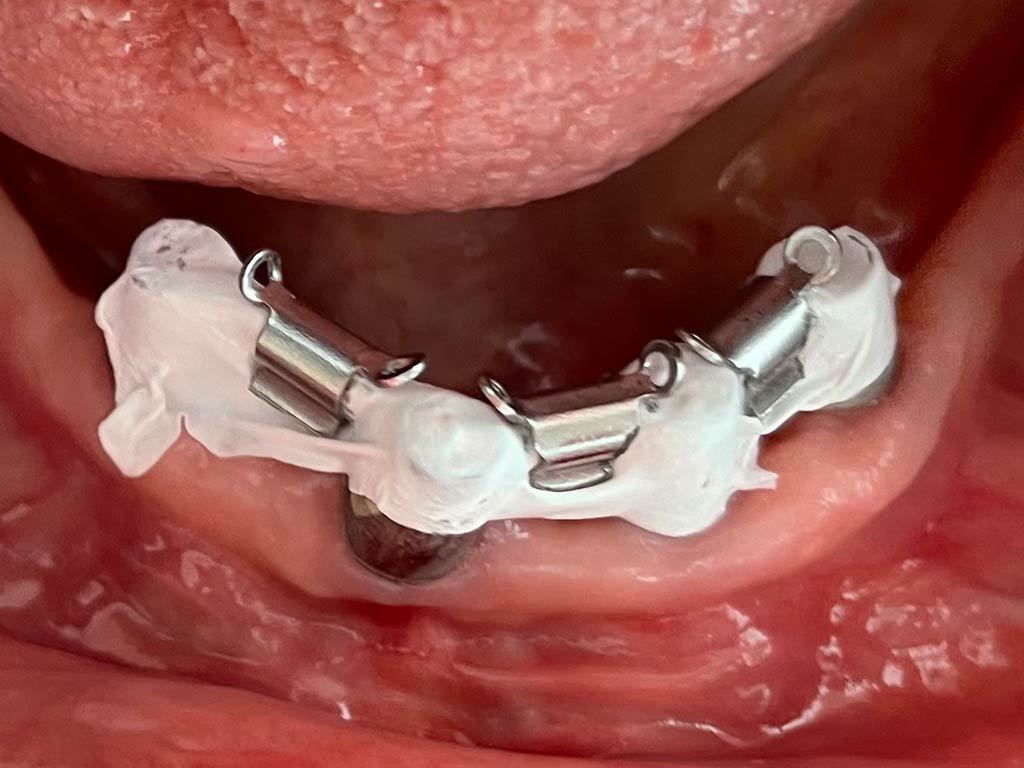

Isolamento di cavalieri nelle protesi overdenture

Posizionato a coprire e proteggere la barra di un overdenture, il TEFLODENT permette di isolare perfettamente i sottosquadri ed agevola il posizionamento dei cavalieri, non aderisce alle resine acriliche e viene rimosso facilmente per rifinire le protesi.